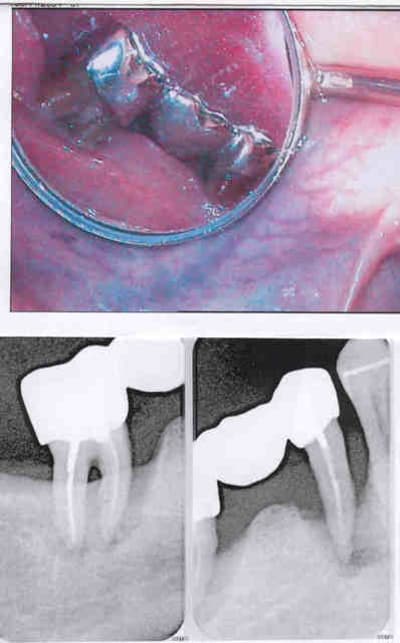

cf photo (désolé mais elle est pas trés lisible): les deux bridges provisoires sont maintenant partcfaitement stables et fonctionnels (ni mobilité ni douleur ni inflammation....)